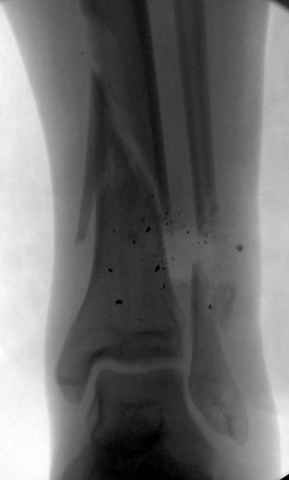

На снимках варианты фиксации малоберцовой:

№ 2-5 при огнестрельном переломе

DK> № 2-5 при огнестрельном переломе

Перелом оскольчатый с диастазом и нефиксация грозила бы ложным

суставом, здесь трудно не согласиться, но... осколок на место поставлен

не был... Вполне возможно, что все и сраслось, но... Никаких проблем в

данном конкретном случае не было? Болей там всяких, тендинитов etc?